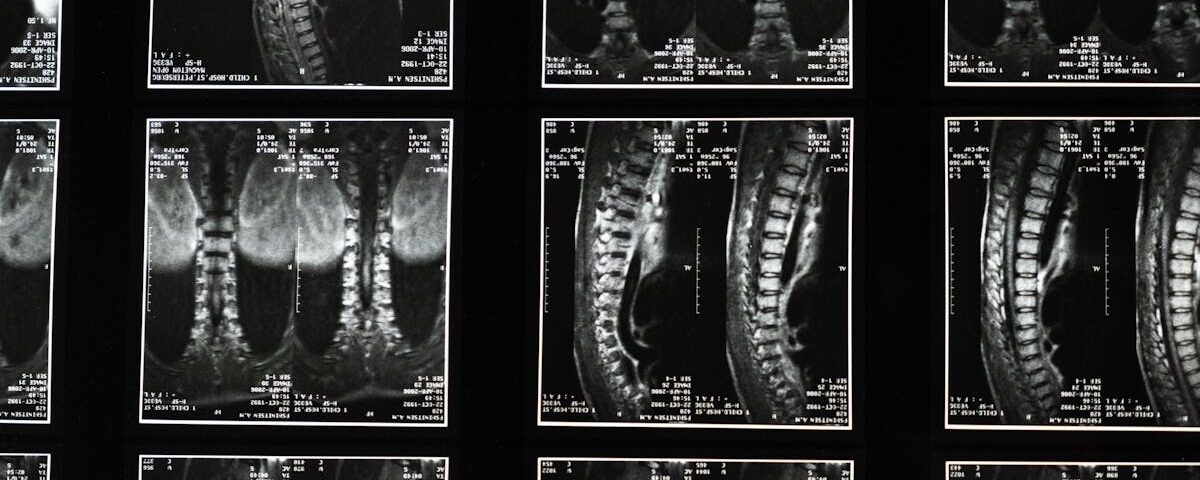

Avant de débuter une thérapie de décompression, il est essentiel d’effectuer une évaluation complète avec un professionnel de la santé. Cette étape vise à identifier les besoins spécifiques du patient et à déterminer si la décompression neurovertébrale est une option adaptée. Il peut être nécessaire de réaliser des examens complémentaires pour évaluer la gravité de la hernies discale et les symptômes présents.

Quels examens permettent de diagnostiquer une hernie discale?

Une IRM ou une radiographie est utilisée pour confirmer le diagnostic d’une hernie discale.

Quels examens sont nécessaires avant de commencer un traitement de décompression?

Une IRM ou une radiographie est généralement nécessaire pour évaluer l’état de la colonne vertébrale.